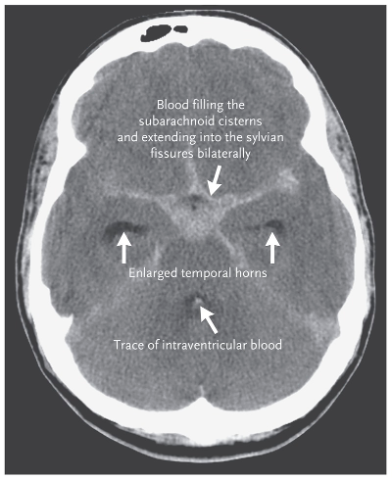

subarachnoid hemorrhage

sudden bleeding into the subarachnoid space (csf mixes with blood)

Symptoms include sudden, severe headache, usually with loss or impairment of consciousness.

frequently a sign of a ruptured aneurysm